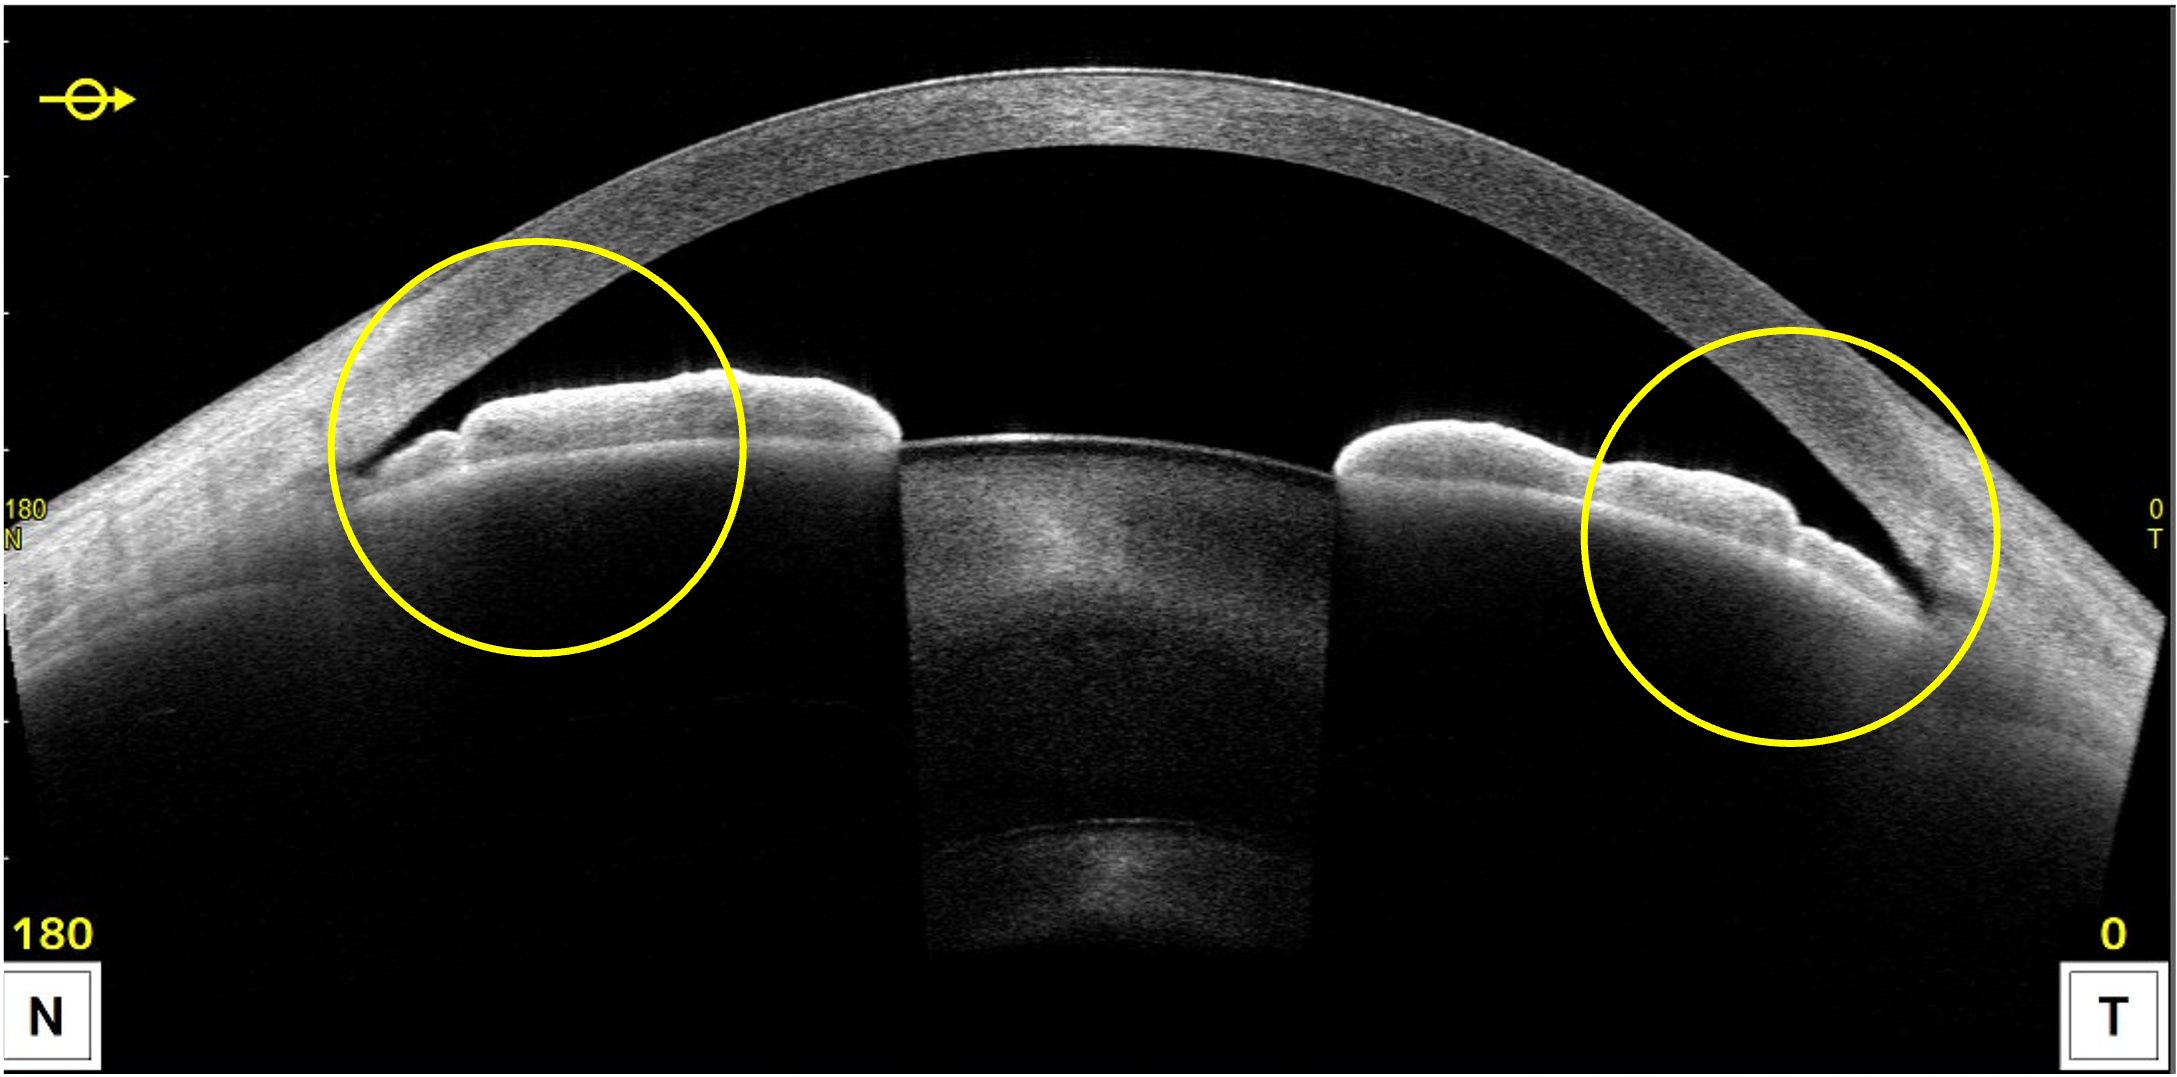

そのため、「前眼部OCT」という検査機器で、眼の断面を詳しく測定し、ぴったりのサイズを選んでいきます。

まず確認するのは、眼の中のスペースです。

ICLは虹彩(茶目の部分)と水晶体の間に入れるので、その空間が十分かどうかを「前房深度」という指標でチェックします。

次に、白目と黒目の境目の幅(WTW)や眼の奥行きを測り、適切なサイズを導き出します。